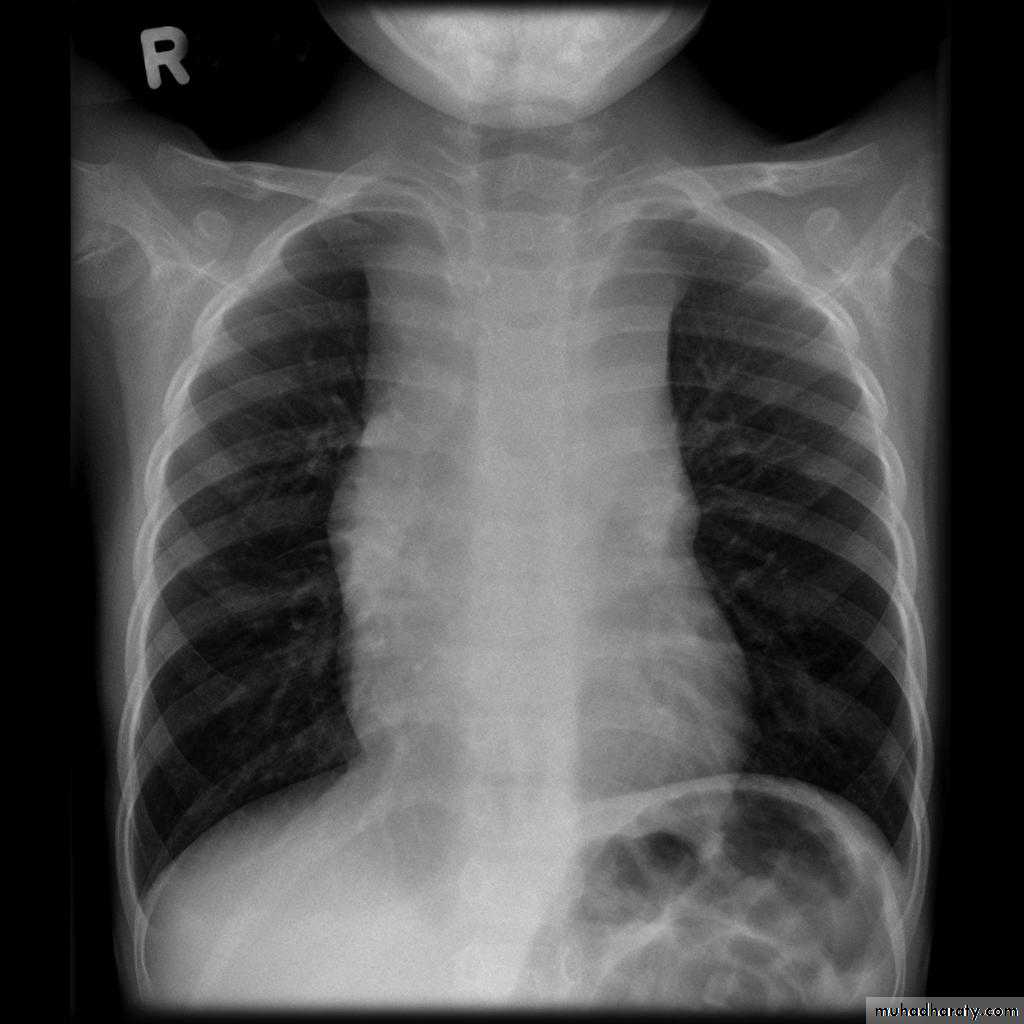

Radiographic featuresPlain film

Typical radiographic features of mitral regurgitation include :

frontal projection

left atrial enlargement

convexity or straightening of the left atrial appendage just below the main pulmonary artery (along left heart border)

double density sign: the right side of the enlarged left atrium pushes into the adjacent lung and creates an addition contour superimposed over the right heart

elevation of the left main bronchus and splaying of the carina

upper zone venous enlargement due to pulmonary venous hypertension

left ventricular enlargement is also eventually present due to volume overload

Features of pulmonary oedema may also be present.